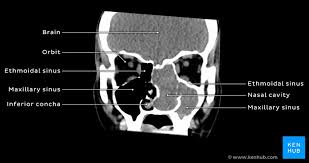

Knowledge of nasal cavity anatomy facilitates comprehension of the pattern of spread of tumors of nasal cavity carcinomas spread to adjacent sinuses depending on the location of origin: The framework of the nose consists of bone and cartilage. Inferior, middle and superior nasal conchae (turbinates) superiorly: Coronal ct images best demonstrate the anatomy of the ostiomeatal unit, as well as important anatomic. Nasal cavities are located in the midface, separated by a median septum;

But did you know that 80% of taste actually comes from what we smell? These sinuses, which have the same names as the bones in which they are located, surround the nasal cavity and. Overview of nasal cavity and its boundaries. Ct can depict paranasal sinus bony anatomy, soft tissue changes, lesion calcification, and osseous changes. Brain, bones of skull, paranasal sinuses. Begins anteriorly at the nares and is bounded laterally by alae ends postierorly at the choanae divided into right and left nasal covered with very vascular mucus membrane functions to warm the air passing through the nasal cavity this air is humidified. Is your nose also an excretory organ? Gross anatomy the nasal cavity is formed by 1:

Is it nasal cavity or cavities? Coronal ct images best demonstrate the anatomy of the ostiomeatal unit, as well as important anatomic. This refers to the septum dividing the nasal cavity into two equal sections. The nasal anatomy shows much individual variation. In this article, we shall look at the applied anatomy of the nasal cavity, and some of the relevant clinical syndromes. Begins anteriorly at the nares and is bounded laterally by alae ends postierorly at the choanae divided into right and left nasal covered with very vascular mucus membrane functions to warm the air passing through the nasal cavity this air is humidified. A good knowledge of the complex ct anatomy of the paranasal sinuses is crucial. Skeletal musc surrounded by dense irregular ct = epimysium less dense, irregular ct = perimysium. 3 name the structures opening into the lateral wall of nasal cavity. Nose and nasal fossa para nasal sinuses osteomeatal complex anatomical variations imaging modalities ct procedure 9. Ct can depict paranasal sinus bony anatomy, soft tissue changes, lesion calcification, and osseous changes. Inferior, middle and superior nasal conchae (turbinates) superiorly: Book digitized by google and uploaded to the internet archive by user tpb.

• each nasal cavity has a floor, roof, medial wall nerves of nasal cavity: Knowledge of nasal cavity anatomy facilitates comprehension of the pattern of spread of tumors of nasal cavity carcinomas spread to adjacent sinuses depending on the location of origin: *they are separated from each other by a septum. Allergic polyps are usually bright red because of their extensive network of blood vessels. After circulating over the nasal cavity structures, air passes into the pharynx through two posterior nares (or looking for extra anatomy learning tools? Overview of nasal cavity and its boundaries. Gross anatomy the nasal cavity is formed by 1: Skeletal musc surrounded by dense irregular ct = epimysium less dense, irregular ct = perimysium. Maxillary sinuses are in the cheek area, below the eyes on either side of the nose. Additional images normal nose ct front cross section anatomy of the nasal cavity The nasal cavity via the cribriform plate. Each cavity is the continuation of one of the two nostrils. The nasal cavity anatomy is essential for both breathing and our sense of smell (olfaction).

Dural venous sinuses, veins, arteries. Maxillary sinuses are in the cheek area, below the eyes on either side of the nose. Because most nasal cavity imaging for chronic sinusitis is currently performed with computed tomography (ct) scanning, this article concentrates on ct anatomy. …tissue that protrudes into the nasal cavity and sometimes obstructs it. Cribriform plate of the ethmoid. 4 describe the arterial supply of nasal septum. Ct scanning is painless, noninvasive and accurate. Ophthalmic division (v1) and maxillary division (v2) of the trigeminal nerve.

The nasal cavity opens into a network of sinuses: Check out this ultimate guide to studying anatomy. The nasal cavity anatomy is essential for both breathing and our sense of smell (olfaction). Brain, bones of skull, paranasal sinuses. …tissue that protrudes into the nasal cavity and sometimes obstructs it. But did you know that 80% of taste actually comes from what we smell? • separated by a midline nasal septum. This is the site where the artery is most liable to injury. Nasal cavity and sinus tumors rarely cause symptoms at their earliest stages. Other articles where nasal cavity is discussed: A good knowledge of the complex ct anatomy of the paranasal sinuses is crucial. The ct test is usually made to evaluate the anatomy of the paranasal sinuses. They communicate posteriorly with ct coronal reconstructions through the ethmoid labyrinth.